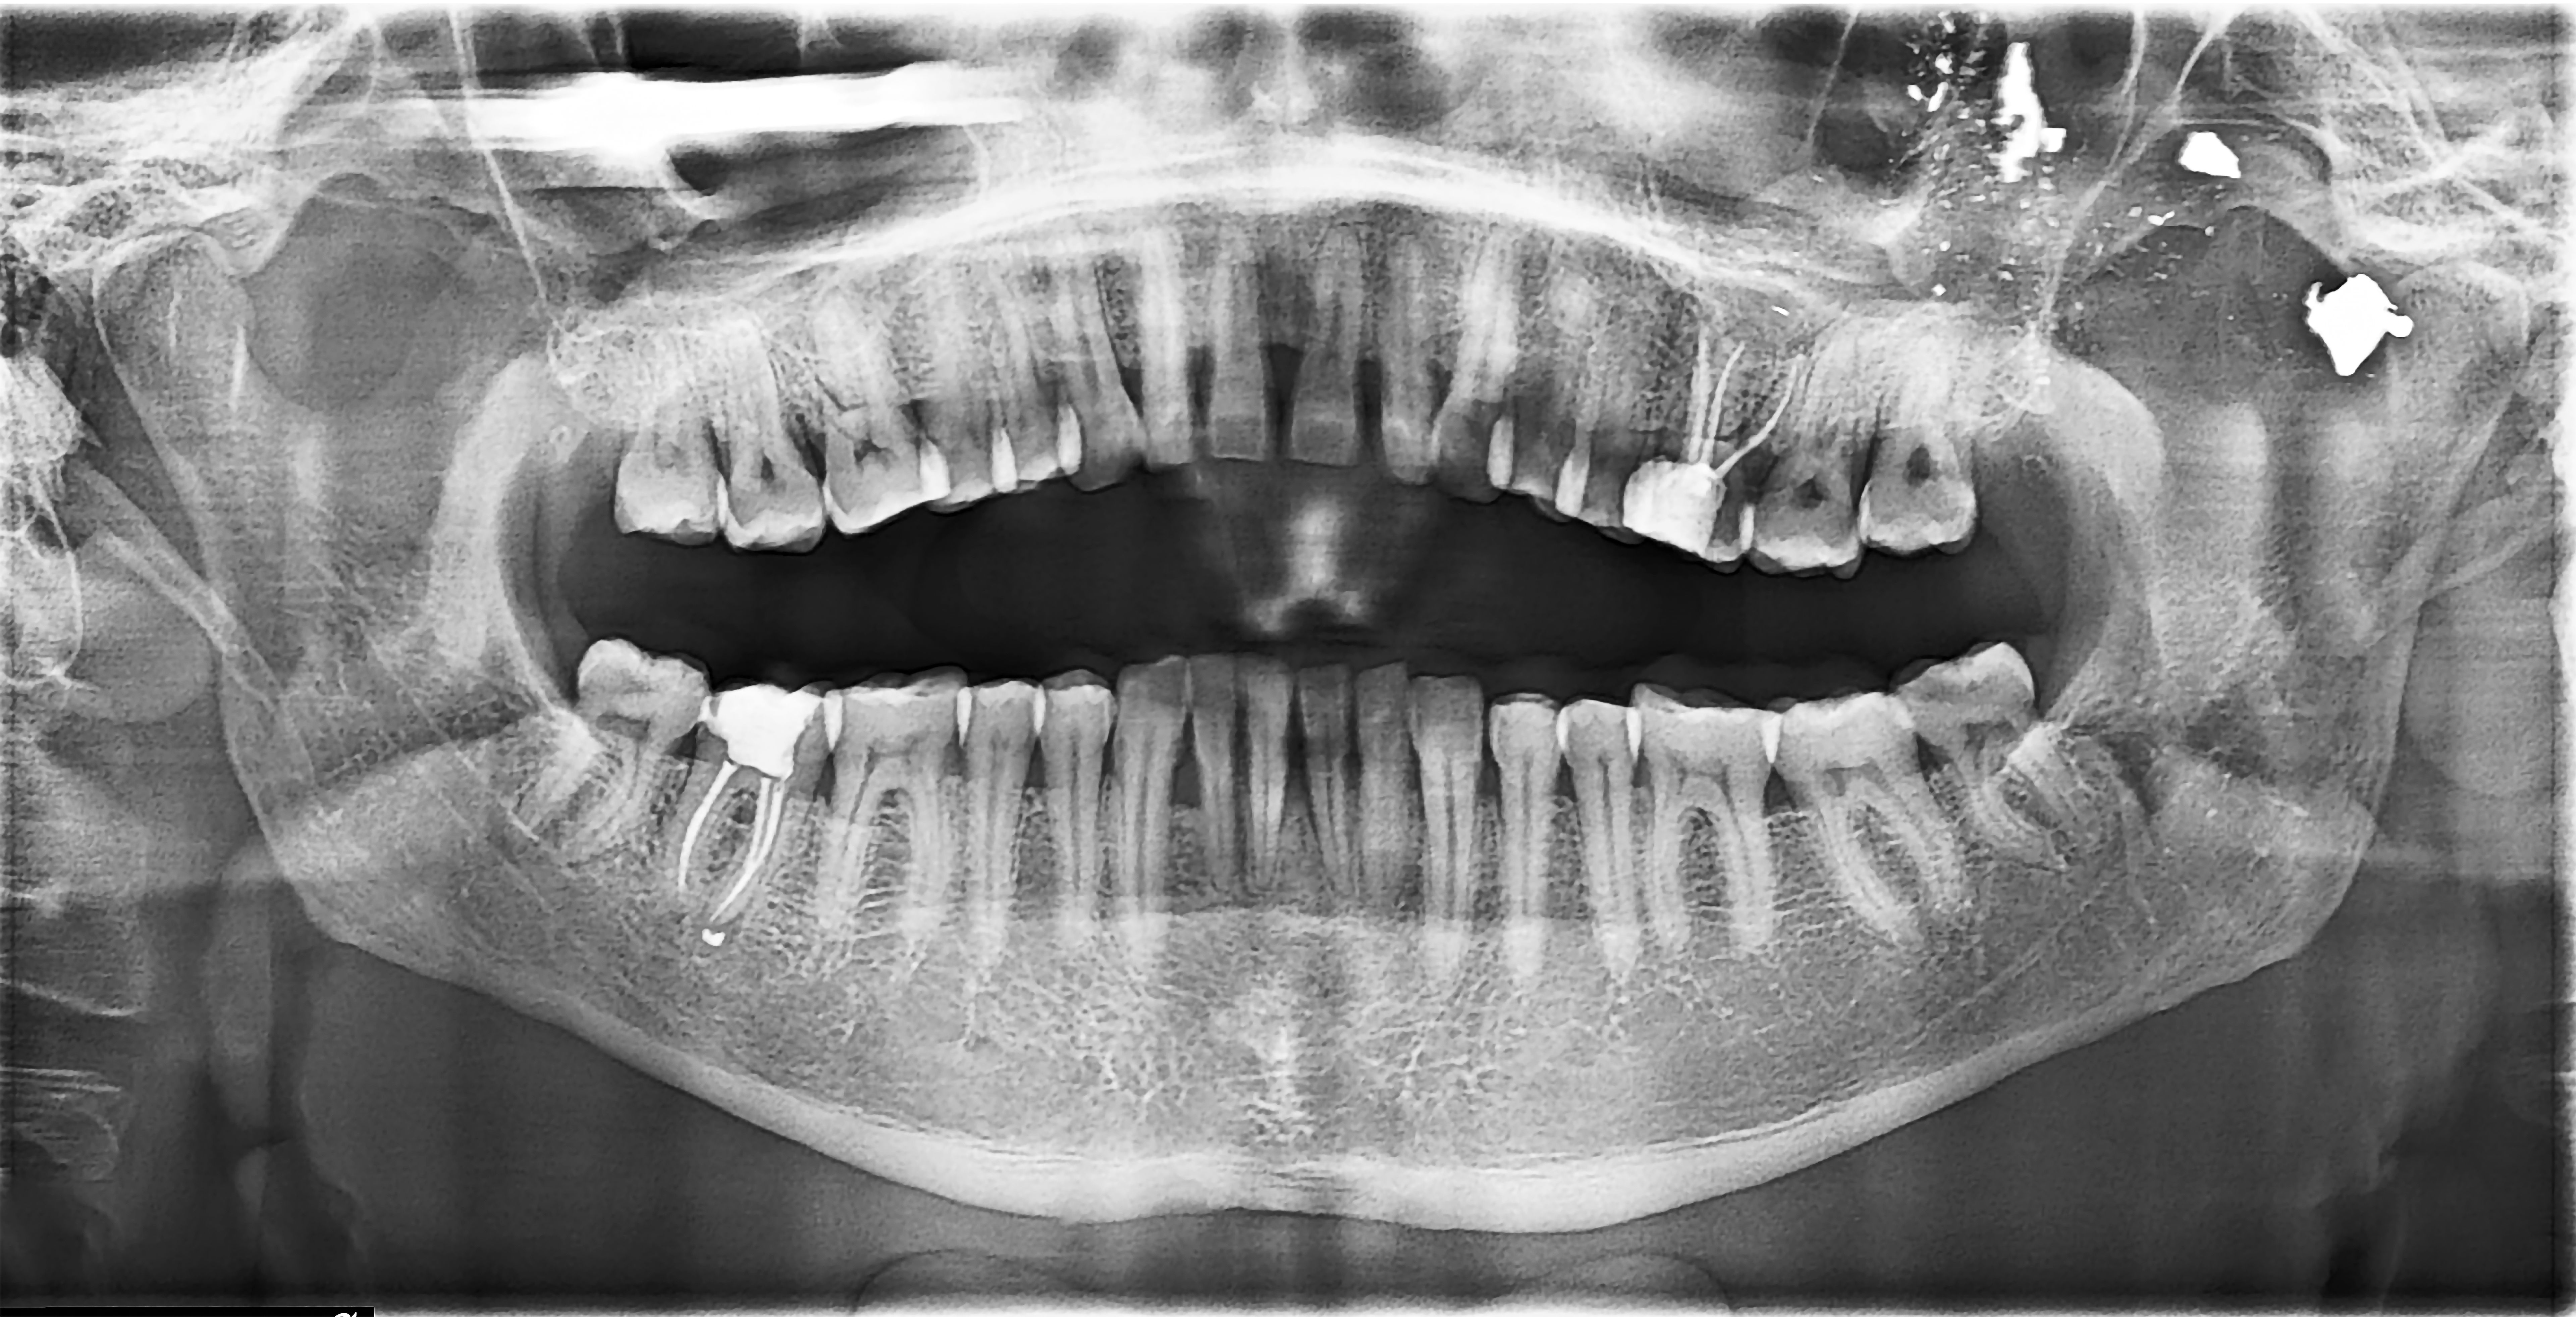

Dental implants have revolutionized the way we approach the problem of missing teeth. Unlike dentures or bridges, dental implants provide a permanent solution that looks and feels like natural teeth. This innovative technology involves the surgical placement of a titanium post into the jawbone, which acts as a root for the artificial tooth.

- Surgery: The implant post is surgically placed into your jawbone.

- Osseointegration: Over several months, the bone grows around the implant, securing it in place.

- Abutment Placement: Once the implant is stable, an abutment is attached to hold the new tooth.

- Crown Placement: Finally, a custom-made crown is placed on top, completing the restoration.